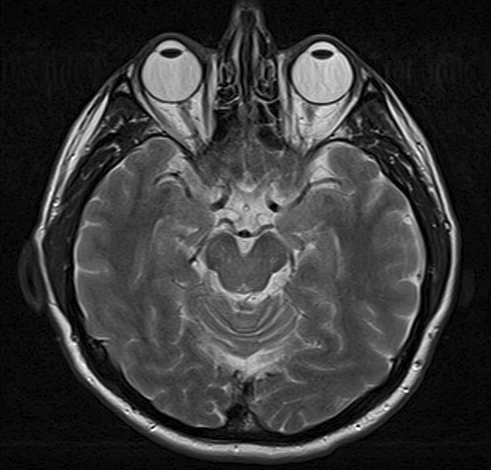

Esta imagen es una resonancia magnética de un cerebro. Los globos oculares de la persona pueden verse en la parte superior de la imagen.

Resonancia magnética

Por Ptrump (Obra propia) vía Wikimedia Commons